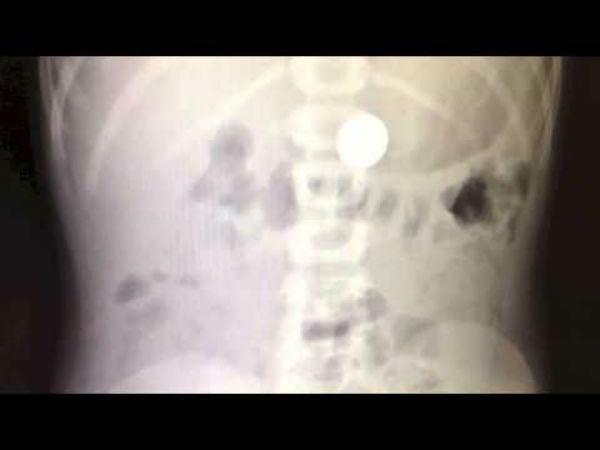

உங்கள் குழந்தை விழுங்கிய காயின் இரண்டு நாளுக்கு மேல் வெளியேறா விட்டால், அது எந்த அறிகுறிகளையும் வெளிப்படுத்தா விட்டாலும் நீங்கள் மருத்துவமனைக்கு கூட்டி செல்வது சிறந்தது. சில நேரம் மருத்துவர் உங்களை மேலும் காத்திருக்க சொல்லலாம் அல்லது குழந்தைக்கு மலம் சீக்கிரம் வெளியேற சில மருந்துகள் தரலாம் மற்றும் மருத்துவர் எக்ஸ் ரே எடுத்து குழந்தையின் வயிற்றில் காயின் எங்குள்ளது மற்றும் அது எதை விழுங்கியது என மிக சரியாக தெரிந்து கொள்ள உதவி செய்வார். குழந்தை காயினை விழுங்கினால் ஆப்பிரேஷன் செய்யும் நிலைமை பெரும்பாலும் வராது. ஒரு வேளை குழந்தை கூர்மையான ஏதேனும் பொருளை விழுங்கி அது குழந்தையின் வயிற்றுப் பகுதியை கிழிக்கும் அபாயம் இருந்தால் அவர் எண்டாஸ்கோபி பரிந்துரை செய்வார்.